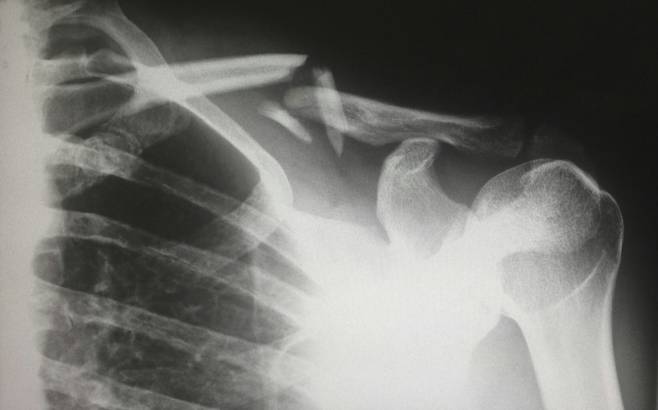

회전근개는 어깨 관절을 둘러싸고 있는 4개의 핵심 근육(극상근, 극하근, 견갑하근, 소원근)으로 구성된 복합체다. 이들은 어깨 관절의 안정성을 유지하고 팔의 정교한 움직임을 가능하게 하는 중요한 역할을 담당한다.

하버드 의과대학을 비롯한 정형외과 전문가들은 “회전근개 파열의 대부분은 한 번의 급성 외상보다는 수십 년에 걸친 미세한 반복 손상의 축적 결과”라며, “특히 팔을 머리 위로 반복적으로 들어 올리는 동작에서 힘줄이 어깨뼈와 지속적으로 마찰하면서 발생하는 충돌 증후군이 주된 원인”이라고 분석한다.

여기에 더해, ‘라운드 숄더’로 대표되는 굽은 등(흉추)은 문제를 더욱 악화시킨다. 등이 굽으면 어깨뼈(견봉) 아래 공간이 물리적으로 좁아져, 팔을 들어 올릴 때마다 회전근개 힘줄이 뼈와 마찰하며 손상되는 견봉하 충돌증후군을 유발한다. 2020년 Journal of Orthopaedic & Sports Physical Therapy에 발표된 메타분석은 흉추 가동성 운동이 어깨 통증을 유의미하게 감소시키고 어깨 관절 가동범위를 개선하는 효과가 있음을 입증했다. 이는 굽은 등을 펴주는 것만으로도 어깨 관절의 생체역학적 환경을 근본적으로 개선할 수 있다는 강력한 과학적 근거다.